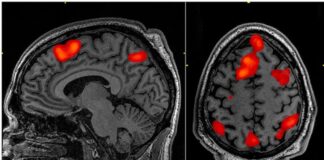

Araştırma: COVID-19 beyini yaşlandırdı!

Britanya’da araştırmaya göre, Covid-19 döneminde insanların beyinleri, 2020 öncesine kıyasla ortalama beş buçuk ay daha hızlı yaşlandı.

Bu artış,...